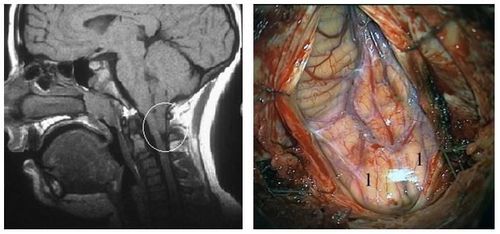

Невралгія трійчастого нерва

Невралгія трійчастого нерва — це хронічне захворювання, яке характеризується повторними нападами інтенсивного, стрілючий біль в:

- районі лобної ділянки,

- очей,

- щік,

- щелеп з одного боку обличчя.

Больовий напад провокуються подразненням так званих «курковий» зон — невеликих ділянок на обличчі, при подразненні яких виникає типове больове відчуття. Напади нестерпного болю змушують хворих припиняти активну діяльність, нехтувати особистою гігієною, біль може вводити людину в депресію.